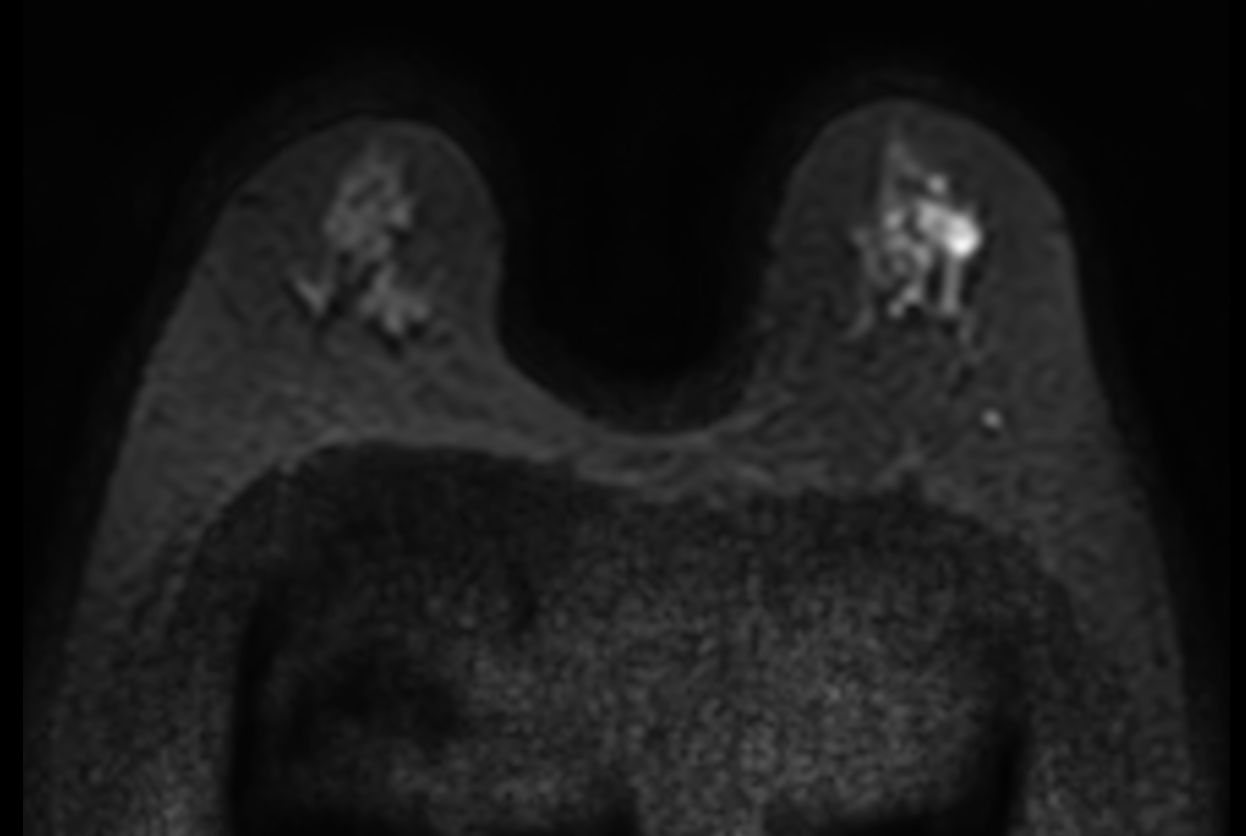

Diffusion (b1500)